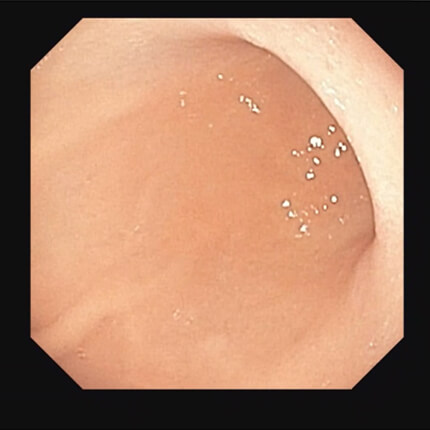

【胃体部】